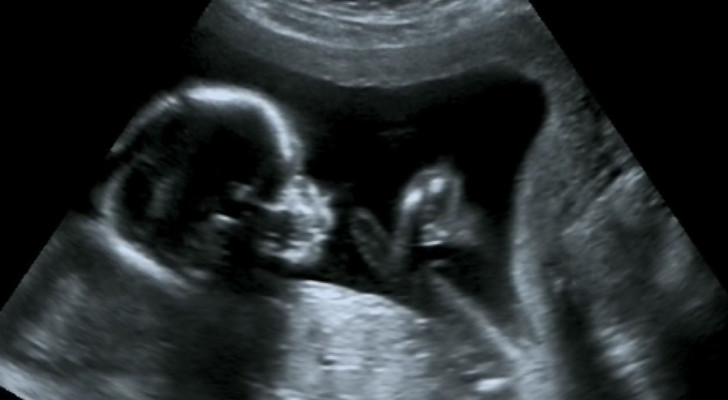

جنين في رحم الأم

كشف باحثون من جامعة فيرارا الإيطالية، في دراسة نشرت بمجلة PLOS One، أن الأجنة الذين يكثرون من التثاؤب بين الأسبوعين 23 و31 من الحمل قد يكونون أكثر عرضة لولادة بأوزان أقل نسبيا. واعتمدت الدراسة على مراقبة 32 جنينا بصحة جيدة عبر التصوير بالموجات فوق الصوتية لمدة 22.5 دقيقة لكل جنين، وسجلت معدلات تثاؤب تراوحت بين صفر وست مرات خلال فترة الرصد، بمتوسط 3.6 مرات في الساعة.

ويعرف التثاؤب بأنه سلوك شائع لدى الفقاريات، إلا أن وظيفته الدقيقة عند الإنسان ما زالت غامضة. ويبدأ الجنين بالتثاؤب منذ الأسبوع الحادي عشر من الحمل، حيث يقوم بفتح فمه وحركات تشبه الشهيق والزفير، رغم عدم وجود هواء يتنفسه.